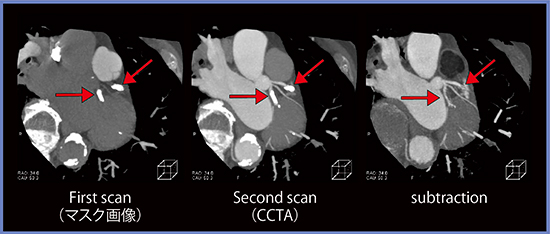

技術的な進歩によって弱点を克服しつつあるCTだが,冠動脈CTAには高度石灰化病変では内腔評価が難しいという限界がある。これを克服する方法として,近年,造影画像からマスク画像を差分して石灰化を除去する“サブトラクションCCTA”の利用が可能になってきた。サブトラクションCCTAでは,高度な非線形位置合わせを併用した差分によって石灰化を除いて,内腔の観察が可能になる(図1)。

しかし,このサブトラクションCCTAでは,造影画像を撮影する一連のシリーズでマスク画像を撮影する必要があり,1回の息止め時間が長くなる。そこで,当院では,テストインジェクション法を用いて上行大動脈への到達時間を求めて,大動脈が染まらない時相でマスク画像を撮影するプロトコルを作成して検査を行っている。一例を示すと,造影剤注入から7秒後に息止めのアナウンス,11秒後にファーストスキャン,25秒後にセカンドスキャンを撮影する。息止め時間は18秒と短くはないが,サブトラクションCCTAが1回の息止め下で20秒を超えない時間で可能となる(図2)。これによって,左冠動脈はサブトラクションによって石灰化が除去され,内腔が確認できる(図3)。吉岡らの報告では,コンベンショナルなCCTAにサブトラクションCCTAを加えることで,高い診断能が得られることが報告されている3)。

図1 サブトラクションCCTAでは石灰化を除去して内腔を観察可能2)

64歳,男性,カルシウムスコア688AU(LAD)

図3 1回の息止め下で撮影された画像からサブトラクション画像を作成